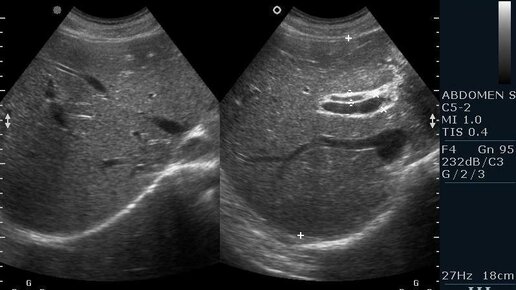

УЗИ органов брюшной полости: что показывает, подготовка и методика проведения

Ультразвуковое исследование (УЗИ) — это безопасный и информативный метод диагностики, который помогает обнаружить патологические изменения внутренних органов. Особенно востребованным остается УЗИ органов брюшной полости, ведь именно эта зона дает о себе знать неприятными ощущениями, тяжестью или болью. Чтобы обследование прошло эффективно, важно понимать, как подготовиться к УЗИ брюшной полости. В этой статье — только проверенная информация от специалистов медицинского центра «Традиции». Ультразвуковая...